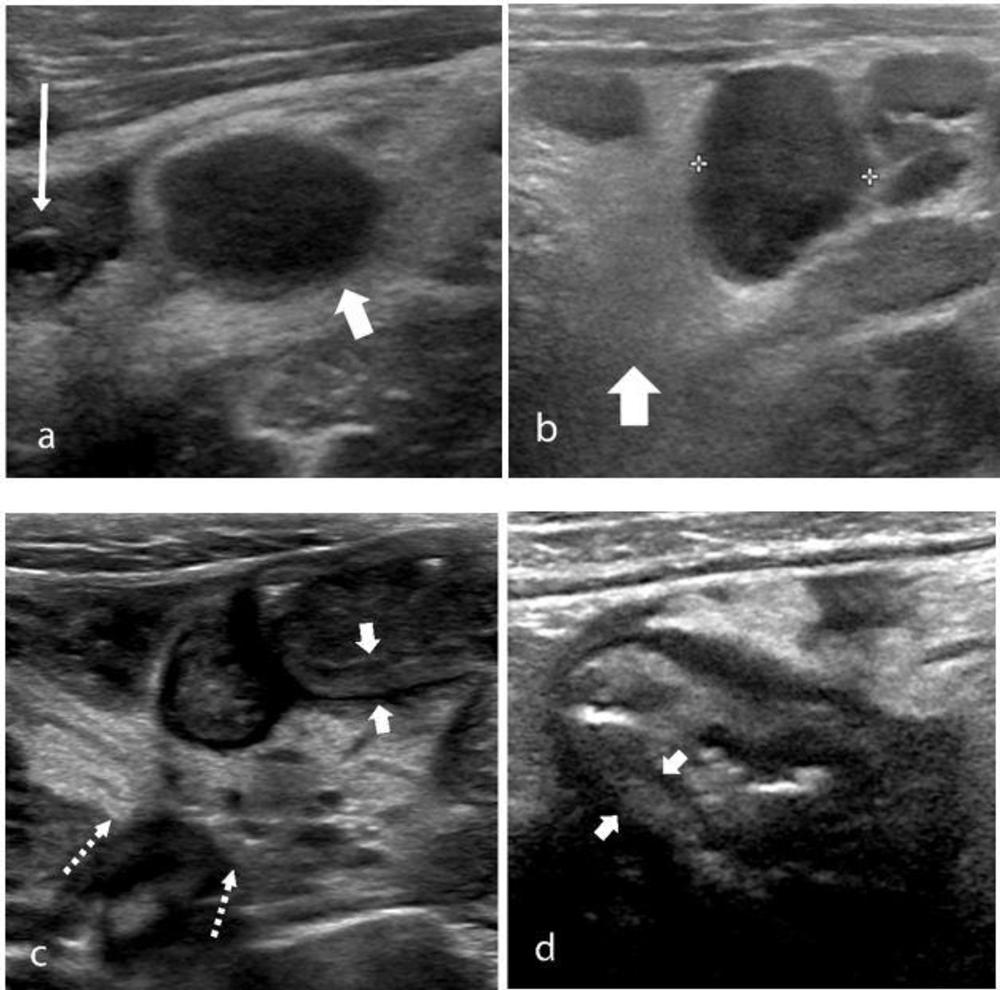

Abdominal ultrasound findings included inflammatory changes within the right iliac fossa, with mesenteric fat stranding, lymphadenopathy and bowel wall thickening, as well as free fluid in the pelvis.

Figure 5. The ultrasound features of right iliac fossa inflammation in four children (a) 7-year-old boy with MIS-C and abdominal pain. High-frequency sonographic image depicts an enlarged mesenteric lymph node within the right iliac fossa (wide arrow), with associated hyperechoic mesenteric fat. The appendix is normal in diameter (thin arrow). (b) 15-year-old boy with MIS-C. Multiple mesenteric lymph nodes within the right iliac fossa, the short axis diameter of the largest lymph node measured 13mm (calipers), with associated hyperechoic mesenteric fat (arrow) were noted on US. (c) 9-year-old boy with MIS-C. US shows loops of thickened small bowel (between solid arrows) with associated hyperechoic mesenteric fat (dotted arrows). (d) 16-year-old boy with severe right iliac fossa pain. High-frequency sonogram shows marked cecal wall thickening (arrows).